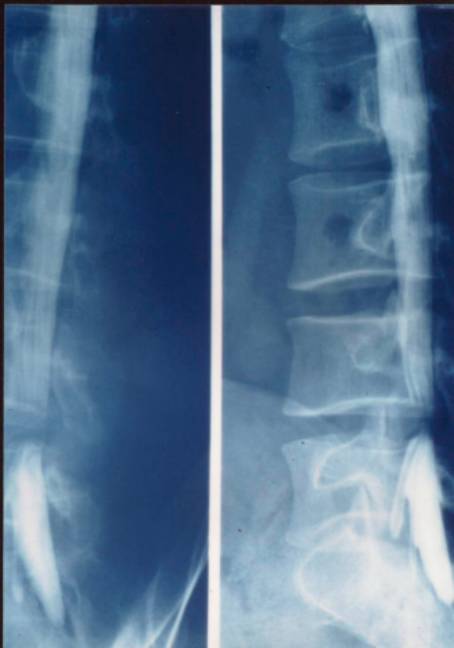

1、X线检查:脊柱曲度的改变;椎间隙变窄;椎体缘骨赘;关节突关节退变肥大;椎体滑脱;神经根管狭窄伴有椎间关节半脱位。

上椎体下缘的后延线不是穿越下椎体上关节突的端,而是穿过中间;正位片显示:正常的“S”弧线消失

X线平片:可明确显示椎管矢状径较正常为狭小,其绝对值于15mm,甚至在12mm以下,个别病例不足10mm。